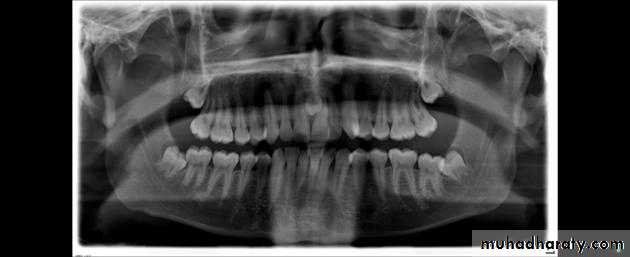

Panoramic films

These are also used to localize impacted teeth in all three planes of space, as much the same as with two periapical films in the tube-shift method, with the understanding that the source of radiation comes from behind the patient; thus, the movements are reversed for position. *(image size distortion; object further away from the image receptor (film) will be depiceted more magnified than objects closer to the film

Radiograph showing impacted maxillary canines with a palatal localization